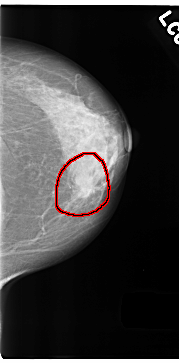

C_0180_1.LEFT_CC

FILE: C_0180_1.LEFT_CC.OVERLAY

TOTAL_ABNORMALITIES 1

ABNORMALITY 1

LESION_TYPE MASS SHAPE LOBULATED MARGINS SPICULATED

ASSESSMENT 5

SUBTLETY 5

PATHOLOGY MALIGNANT

TOTAL_OUTLINES 1

BOUNDARY